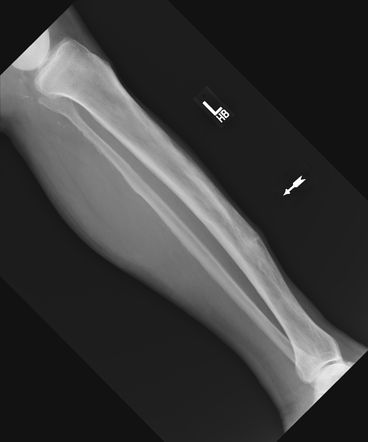

Banana fracture is a complication of Paget's disease. It is a pathological fracture characterized by complete, horizontal fracture. Reference: https://radiopaedia.org/articles/banana-fracture Image via: https://radiopaedia.org/articles/banana-fracture